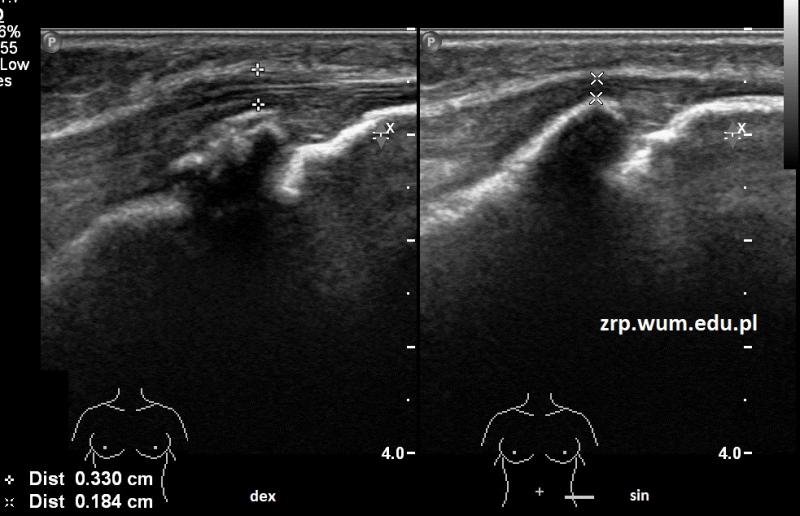

Rozpoznanie: W badaniu USG uwidoczniono nierówny zarys guzowatości kości piszczelowej prawej, z pogrubieniem i przekrwieniem sąsiednich tkanek miękkich - cechy choroby Osgood-Schlattera. Dla porównania prawidłowy obraz guzowatości lewej kości piszczelowej.